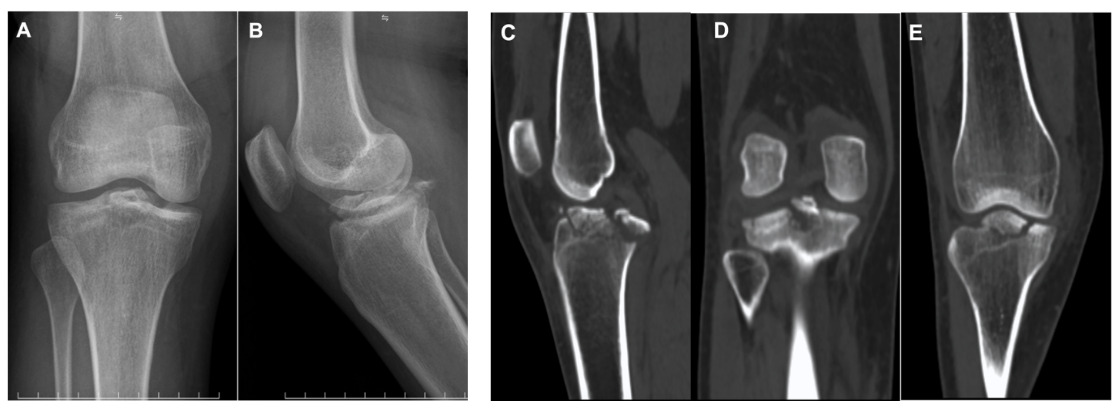

On examination, the right knee demonstrated mild swelling and restricted ROM due to pain. The Lachman’s test and anterior–posterior drawer tests were positive, indicating combined cruciate ligament instability. No associated neurovascular compromise was detected. Radiographic and CT evaluation confirmed completely displaced simultaneous tibial avulsion fractures of the ACL and PCL, with no associated tibial plateau fracture or additional osseous injury (Figure 1). Based on the clinical and radiologic findings, a diagnosis of completely displaced simultaneous ACL and PCL tibial avulsion fractures was established.

Immediate postoperative radiographs demonstrated anatomic reduction of the avulsed fragments (Fig 4A). Follow-up imaging at 1 month confirmed maintenance of stable fixation (Fig 4B). Radiographs and CT at 3 months revealed complete osseous union with preservation of anatomic alignment (Fig 4C, D, E). At 6 months postoperatively, the patient achieved a knee range of motion from 0° to 150°, with negative Lachman’s test and anterior–posterior drawer tests. Functional evaluation demonstrated an objective IKDC grade A, a subjective IKDC score of 100, and a Lysholm score of 100. The patient returned to normal daily activities without pain or residual instability.